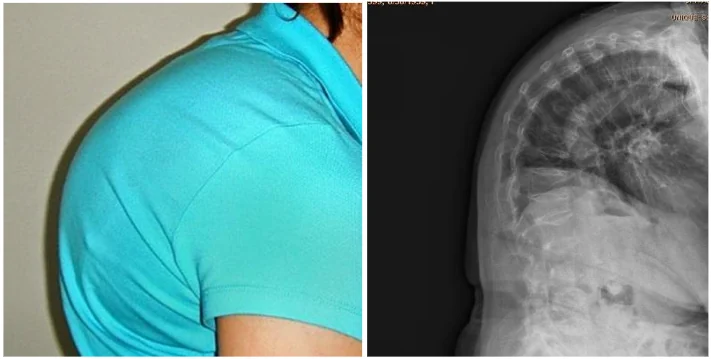

Osteoporoza reprezintă o boală manifestată prin rarefierea ţesutului osos. În unele cazuri ţesutul osos al vertebrelor este într-atât de rarefiat, încât sub acţiunea unei forţe de intensitate mică apare tasarea vertebrală. Partea anterioară a corpului vertebrei se fracturează şi din profil acesta are un aspect clinoid, care repercutându-se asupra poziţiei coloanei vertebrale dând aspectul gârbovit, numit cifoză.

Deformare cifotica a coloanei vertebrale prin multiple fracturi tasare